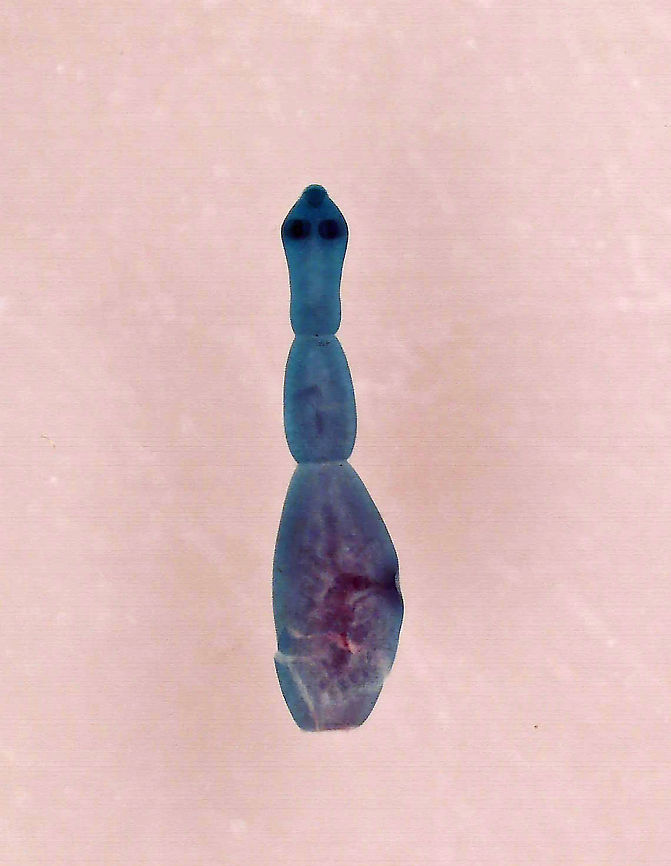

Dog Tapeworm - Echinococcus granulosus

Slide shows an adult tapeworm. It's 4 mm long and has 4 proglottids (segments). A gravid tapeworm can contain 823 eggs.

*Whole mount microscope slide

''Echinococcus granulosus,'' also called the hydatid worm, hyper tape-worm or dog tapeworm, is a cyclophyllid cestode that dwells in the small intestine of canids as an adult, but which has important intermediate hosts such as livestock and humans, where it causes cystic echinococcosis, also known as hydatid disease.